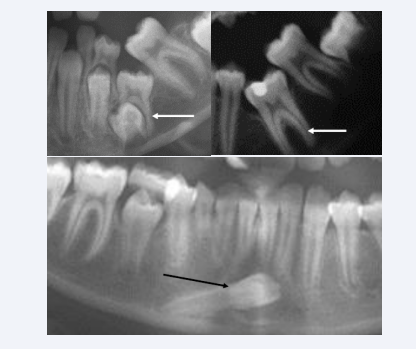

Arrested eruption occur in the primary and permanent dentitions. The etiology behind is often anchylosis-but why anchyloses has developed is not known [33-38]. Ankylotic conditions of a primary molar and of a permanent molar are demonstrated in Figure 20A.

Figure 20 Sections from three orthopantomograms illustrating abnormal development of mandibular teeth. Upper radiographs demonstrate  anchylosed primary molar to the left and anchylosed permanent molar to the right. The anchylosed teeth are marked by white arrows. Lower  radiograph illustrates ectopically permanent mandibular canine located nearly horizontally in the mandibular bone.

Figure 20: Sections from three orthopantomograms illustrating abnormal development of mandibular teeth. Upper radiographs demonstrate anchylosed primary molar to the left and anchylosed permanent molar to the right. The anchylosed teeth are marked by white arrows. Lower radiograph illustrates ectopically permanent mandibular canine located nearly horizontally in the mandibular bone.

Ectopia can be registered in all mandibular permanent teeth. The most seldom type of ectopia seems to be mandibular canine ectopy shown in Figure 20B [39,40]. Several studies on arrested eruption and ectopic eruption have been published with discussion of etiology.